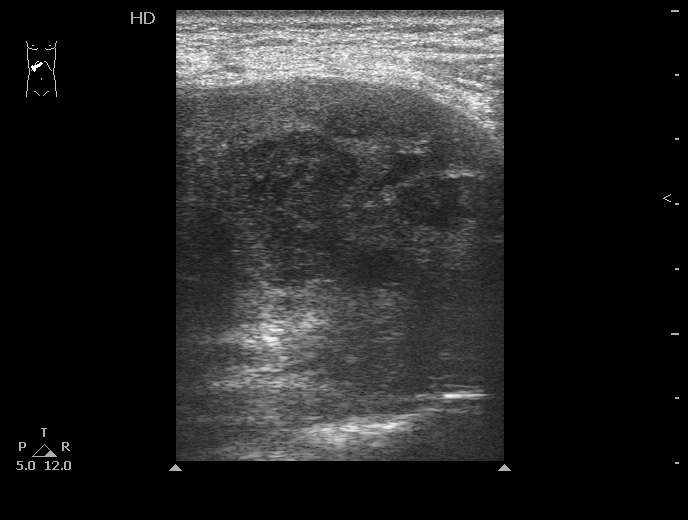

Абсцессы печени

Типичная картина ##1-4:

Гипоэхогенное неоднородное округлое образование, окруженное эхогенным "демаркационным валом"

измененной паренхимы печени.

#5: Эмфизематозный абсцесс - в полости газ, экранирующий его содержимое.